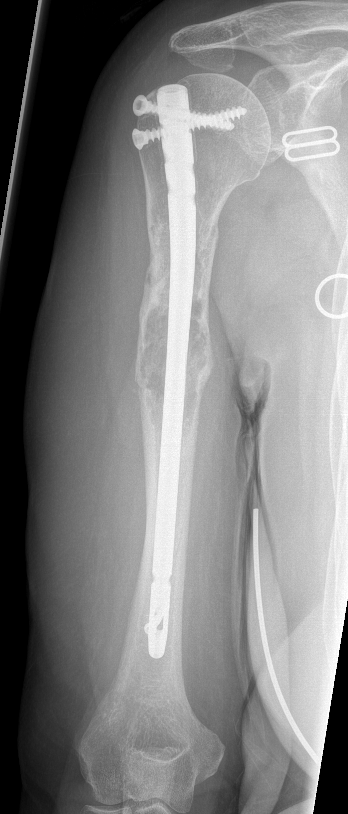

Humeral shaft

Options

Plate +/- cement

IMN +/- cement

Results IMN

Moura et al Rev Bras Ortop 2019

- 86 pathological humeral fractures treated with IMN

- 5% surgical complication rate

- 100 IMN for pathological humerus fracture

- surgical complication rate 11% with cement, 4% without

IMN versus plate

- stabilization of humerus pathological fracture

- broken implant 0% IMN at final follow up

- broken implant 14% plate + cement at final follow up